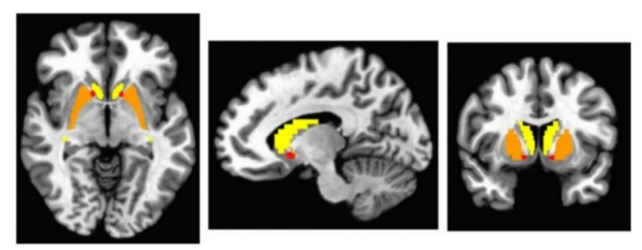

With that context, researchers led by a team from the University of Missouri in the US took a novel approach using a technology known as a DaT SPECT scan, which is typically used to diagnose Parkinson’s in much older people.

“There has been previous work looking into the total amount of dopamine in the brains of people with autism, but we took a new approach by looking at abnormalities in terms of how dopamine is processed in a specific part of the brain called the basal ganglia via these dopamine transporters,” says senior author David Beversdorf, a neurologist from the University of Missouri.

Brain scans on 12 young adults with autism, aged 18-24, revealed abnormal dopamine transporter behavior in two of the 12 participants, with “possible abnormalities” spotted in another two. This means the transporters weren’t as uniformly abnormal or asymmetric as expected.